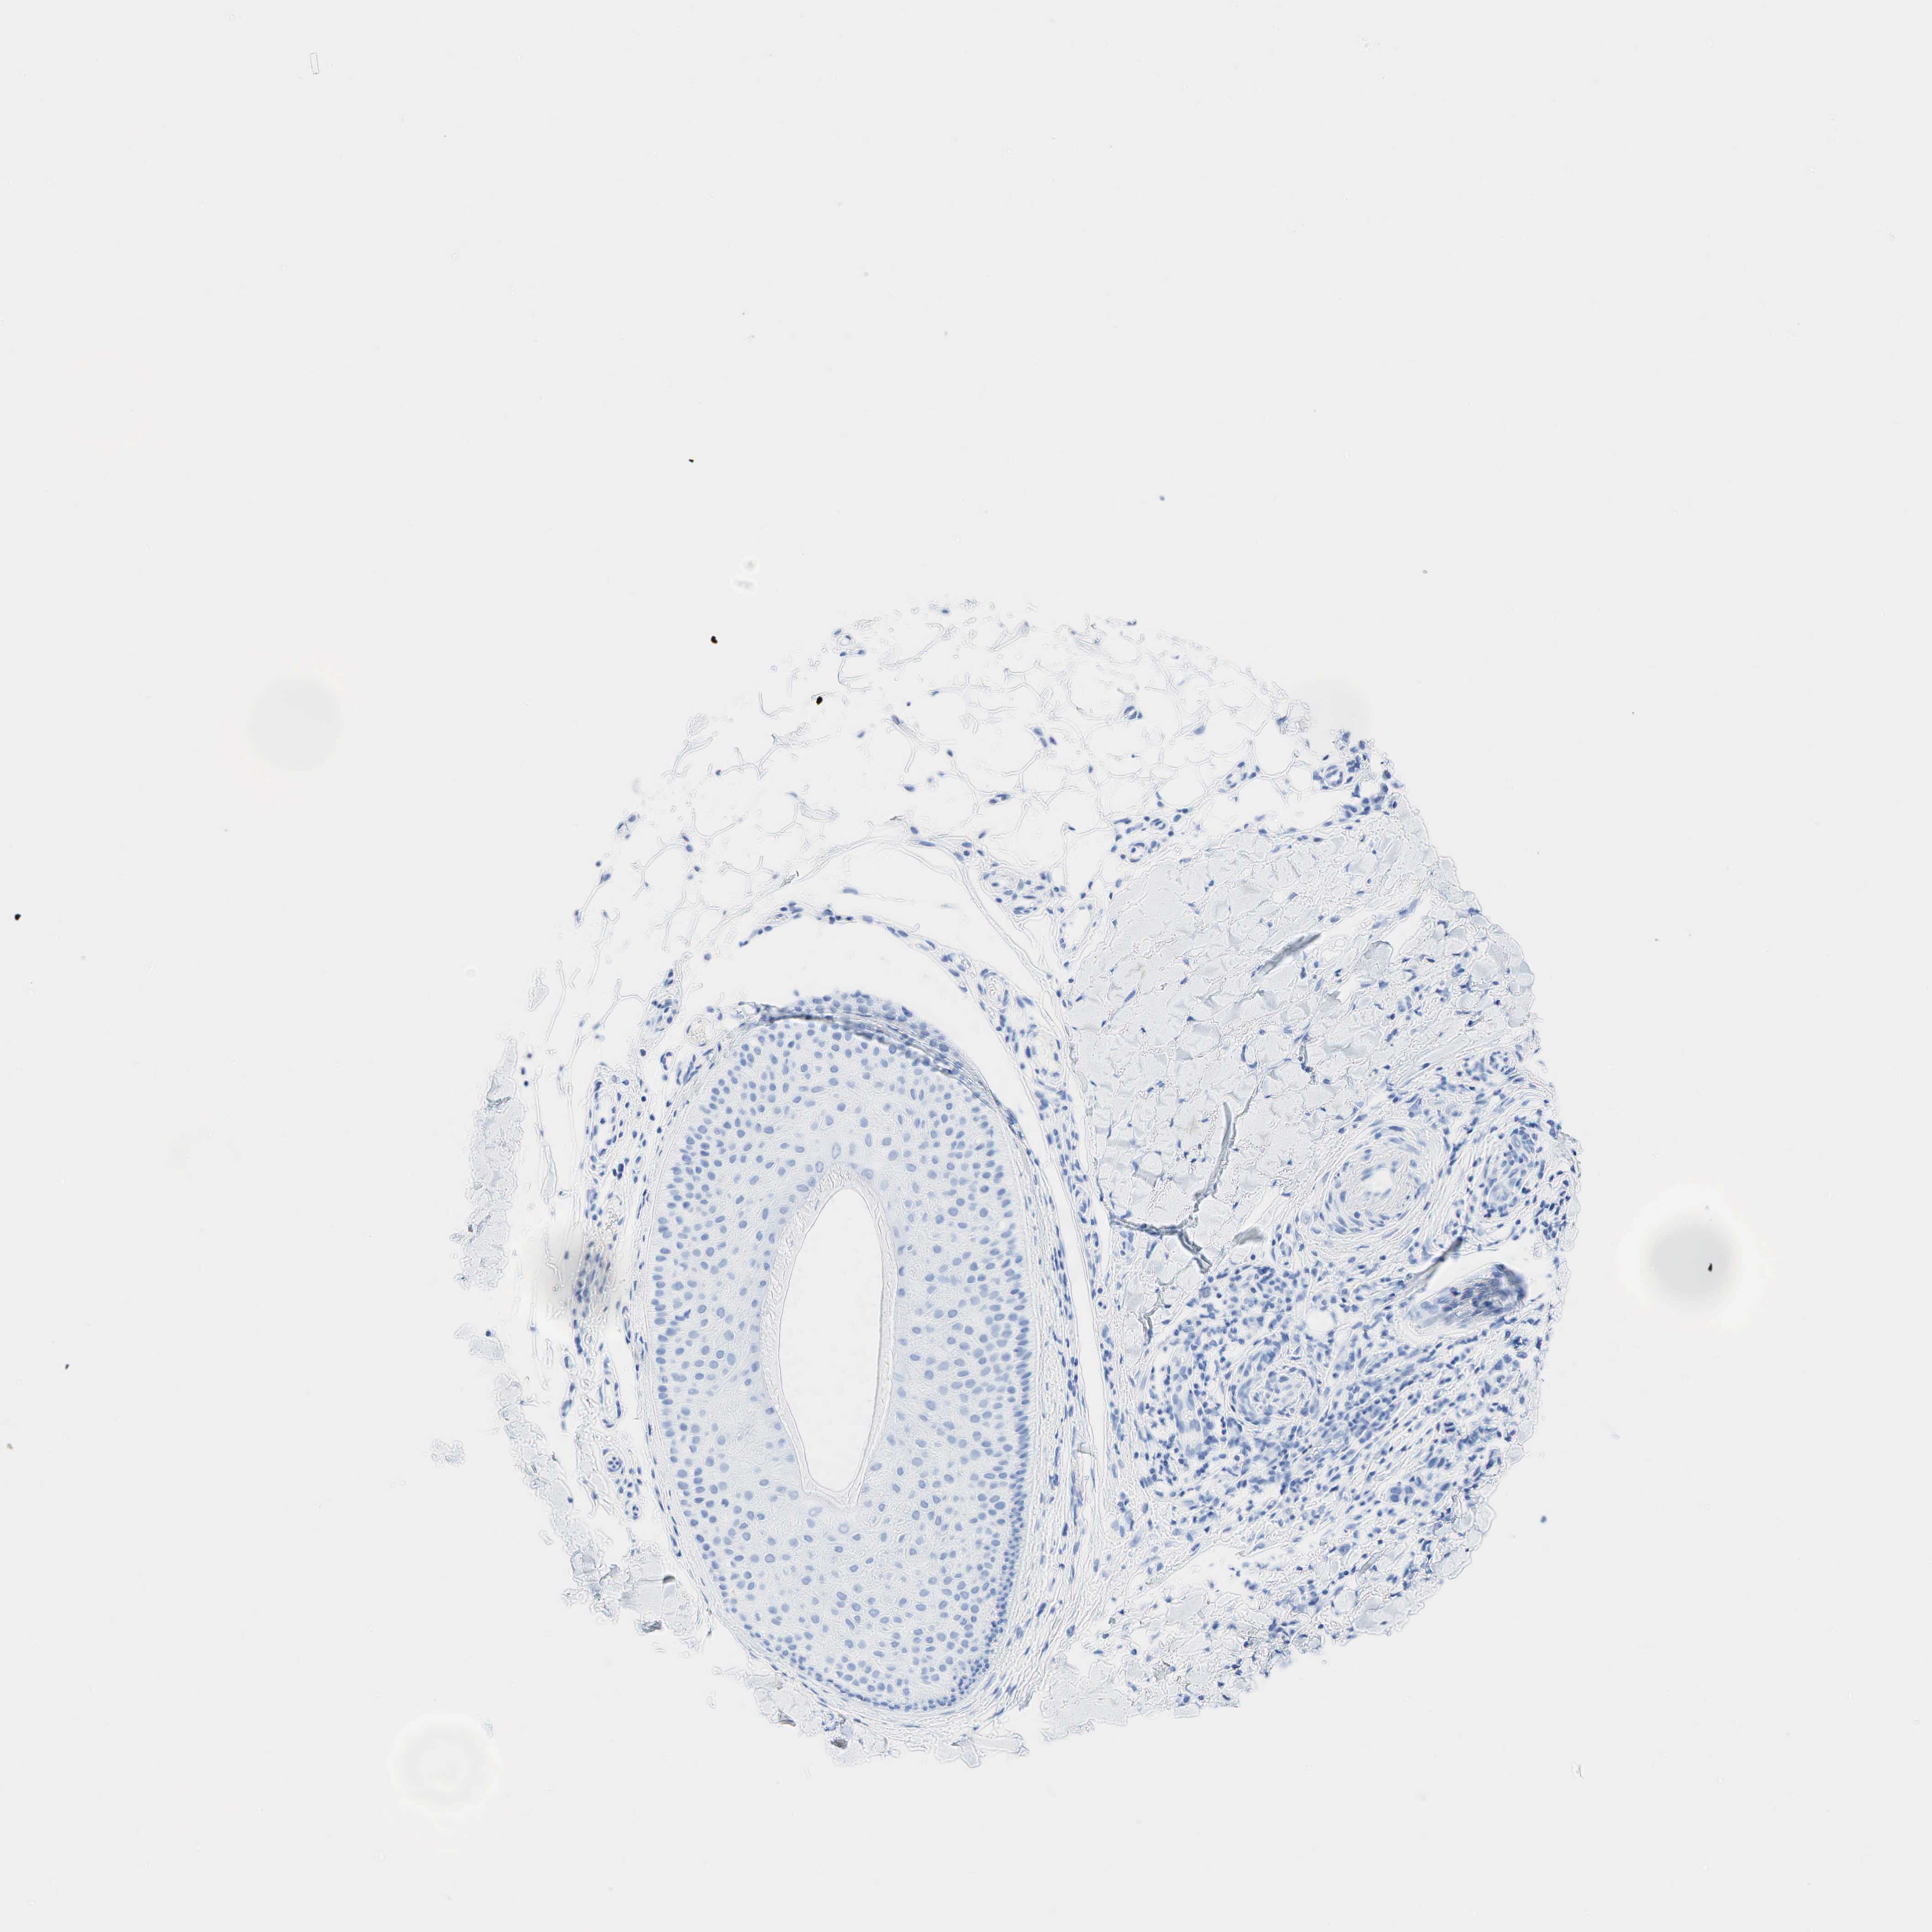

SKIN CANCER - Protein expressioni

A mouse-over function shows sample information and annotation data. Click on an image to view it in a full screen mode. Samples can be filtered based on level of antibody staining by selecting one or several of the following categories: high, medium, low and not detected. The assay and annotation is described here.

Antibody stainingi

Antibody staining in the annotated cell types in the current human tissue is reported as not detected, low, medium, or high, based on conventional immunohistochemistry profiling in selected tissues. This score is based on the combination of the staining intensity and fraction of stained cells.

Each image is clickable and will lead to virtual microscopy that enables deeper exploration of all samples and also displays staining intensity scores, fraction scores and subcellular localization as well as patient and tissue information for each sample.

Antibody HPA019141

Antibody CAB000047

Basal cell carcinoma